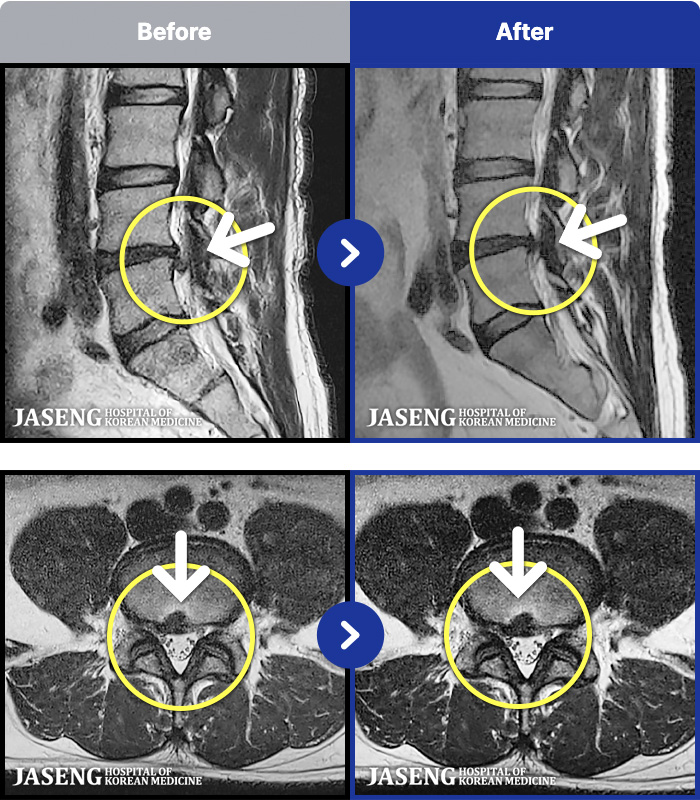

MRI ġ

1,243 MRI ũ ʸ Ȯϼ.